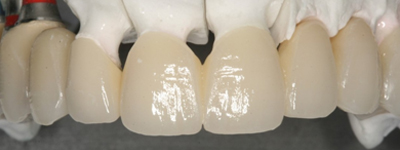

Estética dental

La fresadora dental, en combinación con el escáner más el software de diseño digital de prótesis dentales, son nuestras herramientas más exactas y detalladas para realizar prótesis dentales de máxima precisión y estética.

Utilizamos materiales de alta calidad.